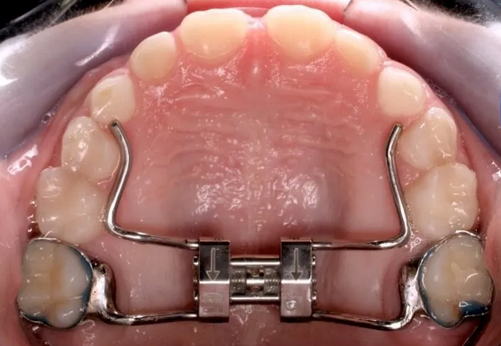

6

Q

device name

A

hyrax